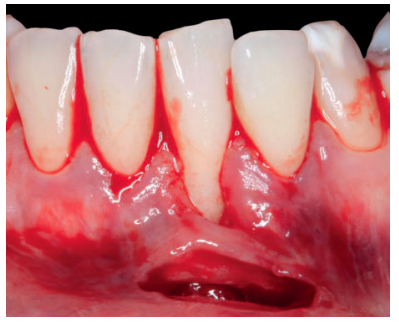

El examen clínico periodontal reveló la presencia de recesión gingival de 5 mm en el diente 31 con una profundidad de sondaje vestibular de 2 mm (perdida de inserción clínica de 7 mm). Presentaba inflamación gingival, además de un frenillo labial inferior insertado en el margen apical de la recesión gingival. El tejido queratinizado faltaba por completo a nivel del diente con recesión (Figura 1). Debido a que el defecto gingival se extendía más allá de la línea mucogingival, así como a la presencia de malposición dentaria, la recesión se categorizó como clase III de Miller6 y RT2 de Cairo7 .

Previamente a la intervención, la paciente se enjuagó durante 1 minuto con un colutorio de clorhexidina. La técnica quirúrgica comenzó con la preparación del lecho receptor, para ello se realizó una incisión sulcular a espesor parcial a nivel de la recesión, se continúo diseccionando apical y lateralmente, extendiéndose de 3 a 5 mm de la recesión para permitir la entrada del ITC y su estabilización. Posteriormente, se realizó una incisión en el fondo de vestíbulo, dejando un puente de tejido que servirá para un doble aporte sanguíneo al injerto (Figura 2).